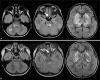

In children, Mycoplasma pneumoniae encephalitis has been characterized by acute onset of an encephalopathy associated with extrapyramidal symptoms and symmetric basal ganglia with or without brain stem involvement on magnetic resonance imaging. Our case, showing unilateral optic neuritis, ophthalmoplegia, no extrapyramidal symptoms, and typical striatal involvement on magnetic resonance imaging, broadens the spectrum of varying clinical manifestations of childhood M. pneumoniae-associated encephalopathy.